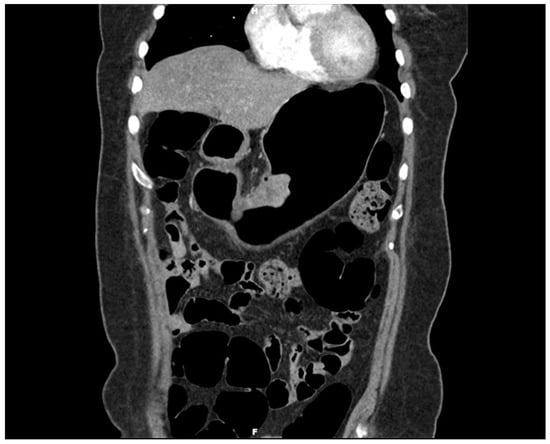

Gastroscopy with three-dimensionally enhanced computed tomography (3D ECT) showing a protruding tumor in the mid-body on the lesser curvature. Gastric duplication cysts (GDCs) are rare congenital anomalies first described in 1911 by Wendel and typically identified in infancy or childhood. Although the exact pathogenesis remains elusive, these cysts are believed to result from aberrations during embryonic development of the foregut [1,2,3]. Characteristically, they share a common wall with the stomach and possess an epithelial lining similar to the gastrointestinal tract [4]. The clinical presentation of GDCs can vary significantly, ranging from asymptomatic to severe abdominal symptoms, depending on their size, location, and the presence of associated complications. Although most GDCs are benign, there have been sporadic reports of malignant transformations within these cysts. Adenocarcinoma is the most commonly reported malignancy arising from GDCs, as evidenced by case reports and small case series [5,6,7,8,9]. Moreover, mixed tumors arising from GDCs are rare. To date, only two cases of mixed adenocarcinoma and squamous cell carcinoma arising from GDCs have been reported [10,11]. Herein, we describe a rare case of mixed adenocarcinoma and squamous cell carcinoma that developed within a GDC. However, it differs from the previous report in that the adenocarcinoma component was pancreatobiliary-type ductal adenocarcinoma. Moreover, this case report is the first to report a mixed pancreatobiliary ductal adenocarcinoma and squamous cell carcinoma in a GDC. It contributes a novel aspect to the scientific understanding of the malignant potential of GDCs and underscores the necessity for vigilance in managing these rare entities. By examining this case, we aim to enrich the discourse on GDCs, particularly their neoplastic capabilities, and provide insights into more effective diagnostic and therapeutic strategies. A 54-year-old Korean woman presented with melena that began a month ago and vomiting with hematemesis over the last 3 days. The patient had no other medical, surgical, or significant personal or family histories. She visited a local hospital for assessment and underwent gastroscopy. Gastroscopy revealed a protruding mass with bleeding in the stomach, which was suggestive of malignancy. The local hospital could not perform a biopsy due to the bleeding, and the patient visited our hospital for further evaluation. A 3D ECT scan revealed a protruding mass in the lower gastric body and enlarged perigastric lymph nodes (this figure). An esophagogastroduodenoscopy revealed an approximately 5 cm-sized protruding mass in the mid-body of the lesser curvature. Endoscopic biopsy revealed a malignancy suggestive of mixed adenocarcinoma and squamous cell carcinoma. PET-CT detected a 5 cm-sized focal hypermetabolic activity in the body of the stomach and focal increased fluorodeoxyglucose uptake in the perigastric lymph nodes; otherwise, the findings were unremarkable. Upon laboratory examination, the results of the complete blood count and routine biochemical investigations were unremarkable. Blood tumor marker tests showed elevated levels of carcinoembryonic antigen (CEA) (52.2 ng/mL; normal range: 0.0–3.4 ng/mL) and carbohydrate antigen 19-9 (CA19-9) (317.0 U/mL; normal range: 0–34 U/mL).